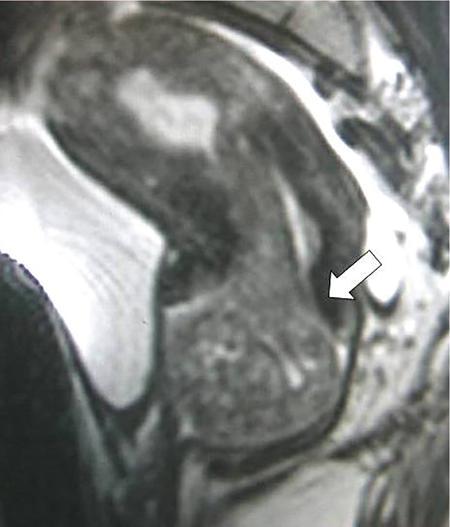

Venkatraman Indiran Bridging vessel sign Multiple vascular channels (white arrows) connecting uterus (black arrow) to an adjacent pelvic mass on imaging studies, is known as the ‘bridging vessel’ or ‘bridging vascular’ sign. Originally described on colour Doppler imaging, but also seen on computed tomography (CT) or magnetic resonance imaging (MRI). Helps in differentiating a mass of uterine origin, typically a subserosal fibroid, from other pelvic masses. Sensitivity and specificity of ‘bridging vessel sign’ in identifying subserosal fibroids range from 90% to 100%. (Best seen when subserosal fibroid is larger than 3 cm in diameter.) Ovarian masses invading the uterus may rarely produce a falsely positive bridging vessel sign. Broccoli sign Submucosal uterine leiomyoma prolapsing into the endocervical canal, along with its stalk in the uterine cavity on sagittal T2-weighted images together is called as ‘broccoli sign’ (white arrow). Submucosal uterine leiomyoma Bunch of grapes Intrauterine mass with cystic spaces without any associated foetal parts on ultrasound (white arrows) classically gives a ‘snow storm’ or ‘bunch of grapes’ appearance. Complete hydatidiform mole Hourglass sign Deep infiltrating endometriosis (DIE) affecting the posterior urinary bladder wall, usually in the midline, causes loss of its distensibility, resulting an hourglass configuration of urinary bladder. Deep infiltrating endometriosis (DIE) Hyperechoic line sign Normal endometrium surrounding the endometrial polyp on ultrasound appear as a hyperechoic rim on transvaginal ultrasound is called as ‘hyperechoic line sign’. Hyperechoic line sign represents a focal intracavitary lesion. Endometrial polyp Indian head dress sign/moose antler sign In deep infiltrating endometriosis (DIE), adhesions between the anterior wall of rectosigmoid and posterior wall of uterus, stretches the muscular layer of the bowel and creates an infiltrative nodule with parallel lines that extend from the adhesion to the rectosigmoid. This is called as ‘Indian head dress sign/moose antler sign’ (white arrow). This is seen on sagittal T2-weighted images as well as transvaginal ultrasound. Deep infiltrating endometriosis (DIE) Interstitial line sign An echogenic line that extends into the upper regions of the uterine horn and borders the margin of the intramural gestational sac is called as the ‘interstitial line sign’ (white arrow). Seen best on transabdominal/transvaginal ultrasound. Specific finding of interstitial pregnancy Mushroom cap sign Mushroom-shaped lesion which is seen displaced into the bowel lumen in patients with solid invasive endometriosis of the rectosigmoid colon on axial or sagittal T2-weighted MRI is called as ‘mushroom cap sign’ (red box and white arrow). Low signal intensity base of the mushroom corresponds to hypertrophy and fibrosis of the muscularis propria, whereas the high intensity cap represents oedematous mucosa and submucosa. Deep infiltrating endometriosis (DIE) Pedicle artery sign Feeding vessel sign Central vessel entering the endometrium from the surrounding myometrium colour Doppler imaging of the endometrium in endometrial polyps is called as pedicle artery sign (white arrow). Endometrial polyps in women with postmenopausal bleeding. (Sensitivity of 76.5%; specificity of 95.3%.) Popcorn ball calcification Dense, amorphous calcifications of uterine fibroids seen on the plain radiographs is called as ‘popcorn calcification’ (white arrow). Confluent, coarse calcification constitutes the most specific radiographic sign of a benign uterine fibroid; but only 10% or fewer of fibroids show calcification. Question mark sign of uterus The uterine corpus that is flexed backward with the fundus of the uterus facing the posterior pelvic compartment and the cervix directed anteriorly toward the urinary bladder, is called as question mark sign of uterus (white arrow). Also called as comma-shaped uterus. 93% specificity and 75% sensitivity in diagnosing adenomyosis uterus. Sliding organs’ sign When the uterus and ovaries glide freely over the posterior and anterior organs (such as rectum and urinary bladder, respectively) during real-time dynamic transvaginal sonography, it is called as ‘positive sliding organs’ sign’. In case of adhesions due to endometriosis, free gliding of organs is absent and is called as negative sliding sign. Snowstorm sign Grainy appearance with low-level homogeneous internal echoes which move slowly downward due to their viscosity seen in endometrioma on transvaginal ultrasound is called as snowstorm sign. Endometriomas Split fibre sign Presence of curvilinear T2 hypointense strands within the degenerated leiomyoma separated by the fluid accumulation and oedema is called as the ‘split fibre’ sign. Split fibre sign on T2-weighted MRI can be used to differentiate hydropic degeneration from other conditions like malignant change. Three-line sign or triple line sign or trilaminar appearance Shortly before ovulation, two additional bright linear echoes outline two hypoechoic layers of endometrium with a central hyperechoic line in the endometrium (white arrow). It is called as the ‘three-line sign’ or ‘triple line sign’ or trilaminar appearance. A triple-line pattern with a moderate endometrial thickness is associated with a good clinical outcome on in-vitro fertilization. Venetian blind shadowing Also known as ‘rain shower’ appearance Heterogeneous myometrial appearance due to hyperechoic heterotopic endometrial tissue and hypoechoic hyperplastic smooth muscle appearing as vertical linear bands of shadows on ultrasound is called as ‘Venetian blind shadowing’. Classically described in uterine adenomyosis; sometimes in uterine fibroids also. Bead on strings sign Thickened endosalpingeal longitudinal folds within a dilated fallopian tube without wall thickening appears as small mural nodules on cross-sectional images on ultrasound is called as ‘bead on strings’ appearance. Seen in chronic salpingitis Beaded tube Multiple constrictions along the course of fallopian tube may form due to scarring is seen in genitourinary tuberculosis and shows a ‘beaded’ appearance. Female genital tuberculosis Cogwheel sign Thickened endosalpingeal longitudinal folds within a dilated fallopian tube with thickened wall appears as small mural nodules on cross-sectional images across the long axis of the fallopian tube on ultrasound (white arrows) produce a characteristic ‘cogwheel’ appearance. Seen in acute salpingitis. The presence of thickened longitudinal folds is pathognomonic for hydrosalpinx. Cobblestone tube Rounded filling defects in cases of fallopian tube tuberculosis are called as the cobblestone pattern. Is an effective radiographic sign of intraluminal scarring and adhesions. Female genital tuberculosis Golf club tube Occlusion of the isthmus or fimbrial end of the fallopian tube and filling up of the tube with serous or clear fluid produces a moderate dilatation at the fimbrial end, produces a ‘golf club–like appearance’. Female genital tuberculosis Halo sign Thin radiolucency seen separating the loculated peritubal collection from the dilated tube, is known as the ‘halo sign’. This radiolucent halo represents the thickened wall of the tube. Female genital tuberculosis Incomplete septation sign Thin linear structures appearing to protrude into the tubular cystic adnexal structures, but not touching the opposite walls is called ‘incomplete septation sign’ of hydrosalpinx. Apparent septae are due to apposition of the inner walls of the dilated and folded fallopian tube. Hydrosalpinx Pipe stem tube Rigid contour of the fallopian tube seen in cases of fallopian tube tuberculosis is called as ‘pipe stem appearance’. Female genital tuberculosis Leash sign Typical eccentric leash of vessels on colour Doppler (white arrow) showing a low resistance placental type of flow on spectral Doppler in fallopian tube ectopic pregnancies is called as leash sign.